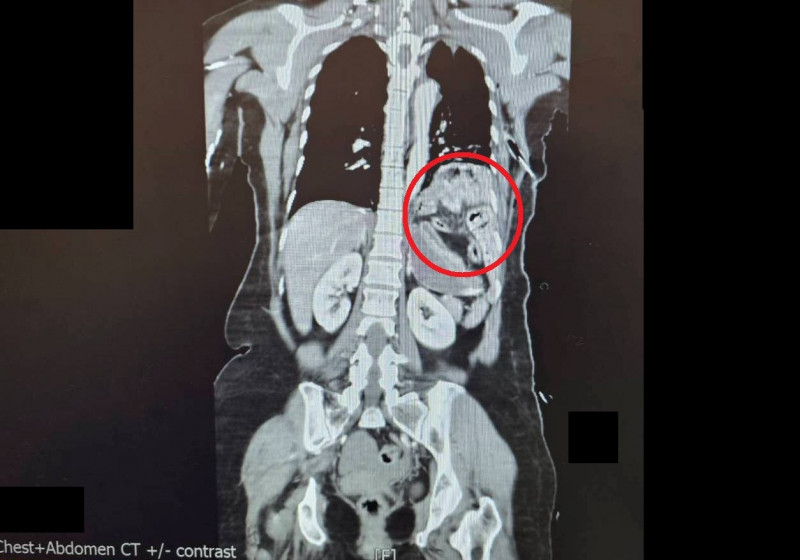

大千醫院指出,陳女被送抵急診時,出現嚴重的雙側氣胸與皮下氣腫,呼吸極度困難。經全身電腦斷層掃描發現,強大的撞擊力導致她的左側橫隔膜破裂,原本應在腹腔的胃部及部分腸道,竟位移進入左側胸腔,嚴重壓迫左肺,導致肺部無法擴張。此外,檢查更發現其下腹部大量出血(腸繫膜血管破裂)、左腳踝骨折,背部還有大面積的2至3度擦燙傷,傷勢遍布全身。

外科醫師馮啟彥評估後,決定採取難度較高的腹腔鏡微創手術。馮啟彥說:「透過腹腔鏡的3個小傷口,先往左上腹腔將移位的胃腸道拉回原位,並修補破裂的橫隔膜;接著隨即將鏡頭倒轉往骨盆腔,修補兩處大量出血的腸繫膜血管。」這種方式不僅避開了大面積傷口,也大幅減少病人的體力消耗。